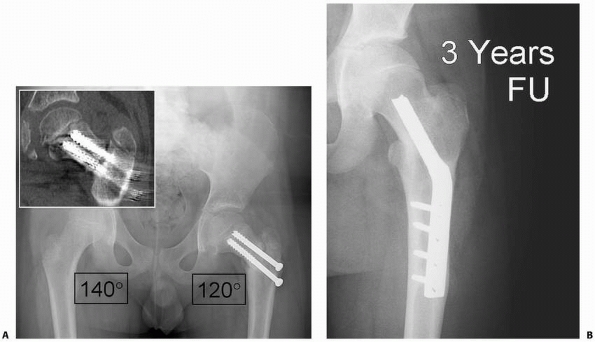

|  |

| FIGURE 21-15 A. A 10-year-old boy with a type III fracture treated without cast immobilization develops progressive varus deformity 4 months after surgery. Inset CT scan demonstrates delayed union. Valgus osteotomy is indicated for his progressive varus deformity and delayed healing. B. Three years after valgus osteotomy, the fracture is healed and the deformity corrected. |